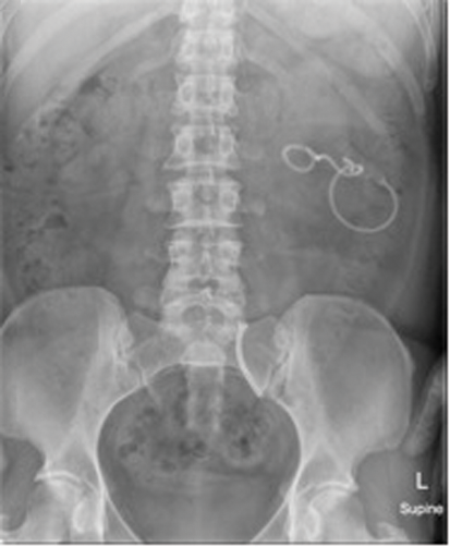

Case 3

Image 1.

Image 2.

- What do the X- Ray KUB images show?

Image 1: Memokath in left mid-ureter plus left nephrostomy.

Image 2: Memokath migration into bladder.